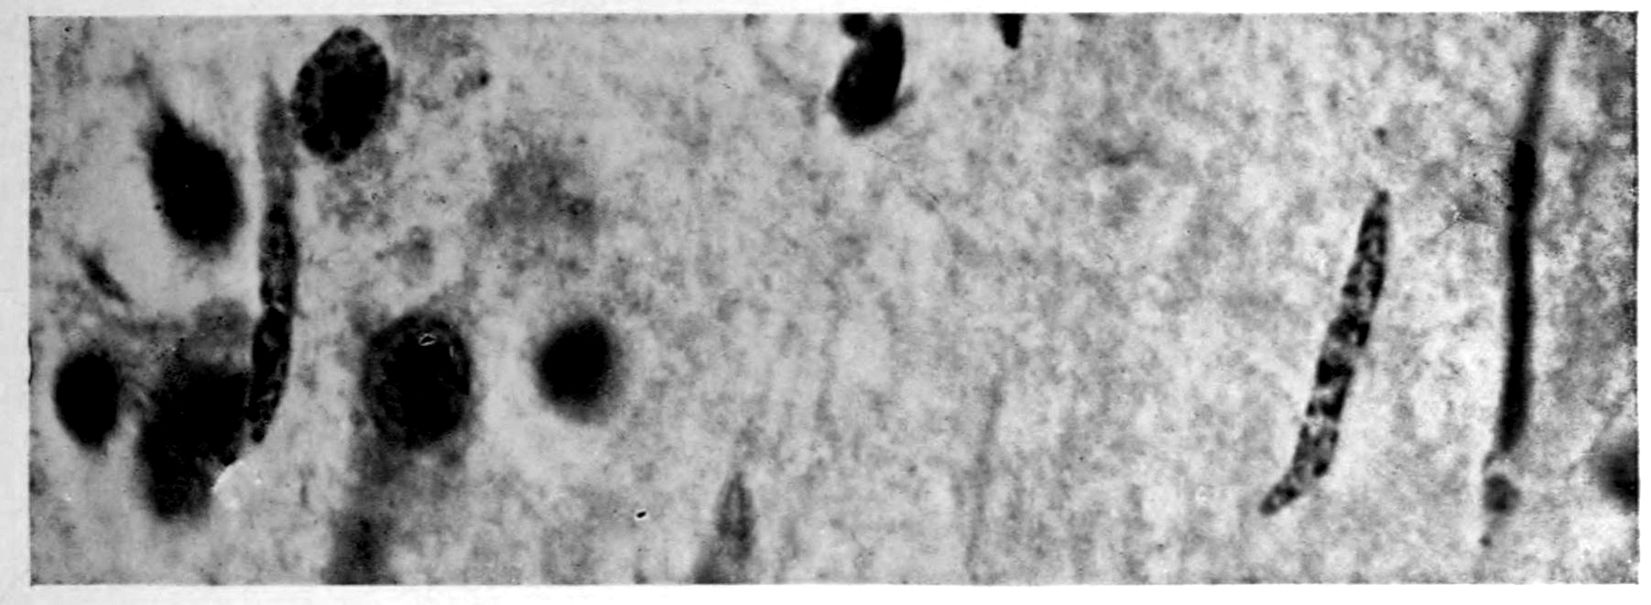

A. Normal postcentral cortex. (Compare B.)

B. Nerve cell losses. Perivascular deposits of mononuclear cells, amongst which are numerous plasma cells. Note decrease in number of nerve cells. Note irregular disposition of nerve cells. From paretic neurosyphilis.

Apparent new formation of small blood vessel. Photographed by Dr. A. M. Barrett.

Rod cells (Stäbchenzellen) in paretic neurosyphilis. Photographed by Dr. A. M. Barrett.

Granular ependymitis—microscopic appearance of a marked example of “sanding” of ventricle.

41Characteristic and constant in paretic neurosyphilis is the Plasmocytosis and Lymphocytosis, Perivascular in distribution about small cortical vessels. There is also a characteristic (though characteristically less prominent) Plasmocytosis and Lymphocytosis, Meningeal in distribution. The pleocytosis of the spinal fluid, almost constant though variable in amount in life, is an indicator of the meningeal picture and less directly of the parenchymatous picture.

Granular Ependymitis (“sanding” of ventricle floors) is characteristic and may be regarded as part of the parenchymatous picture. This ependymitis is an indicator how chemical changes could be readily produced at least in the ventricular fluids, since the limiting membranes of the nerve tissue are here subject to multiple breaks. The “sanding” is a neuroglia reaction to these multiple small breaks (Weigert’s explanation).